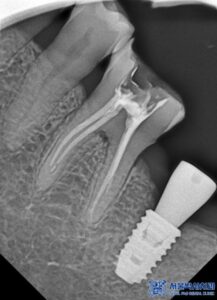

환자분은 좌측 아래쪽 어금니가 없는 상태였고,

오랫동안 방치되어 치조골(잇몸뼈)의

변화가 일부 있었습니다.

하지만 다행히도 임플란트를 식립하기에

충분한 골량이 유지되고 있었고,

무절개 방식으로 빠르게

임플란트를 진행할 수 있었습니다.

무절개 방식은 컴퓨터 분석을 통해

미리 임플란트의 식립 위치를 시뮬레이션하여,

수술 시 오차를 줄여주는 방법입니다.

수술 가이드를 활용하여 정확한 위치에

임플란트를 심기 때문에,

잇몸을 절개할 필요 없이 간편하고

안정적인 수술이 가능합니다.